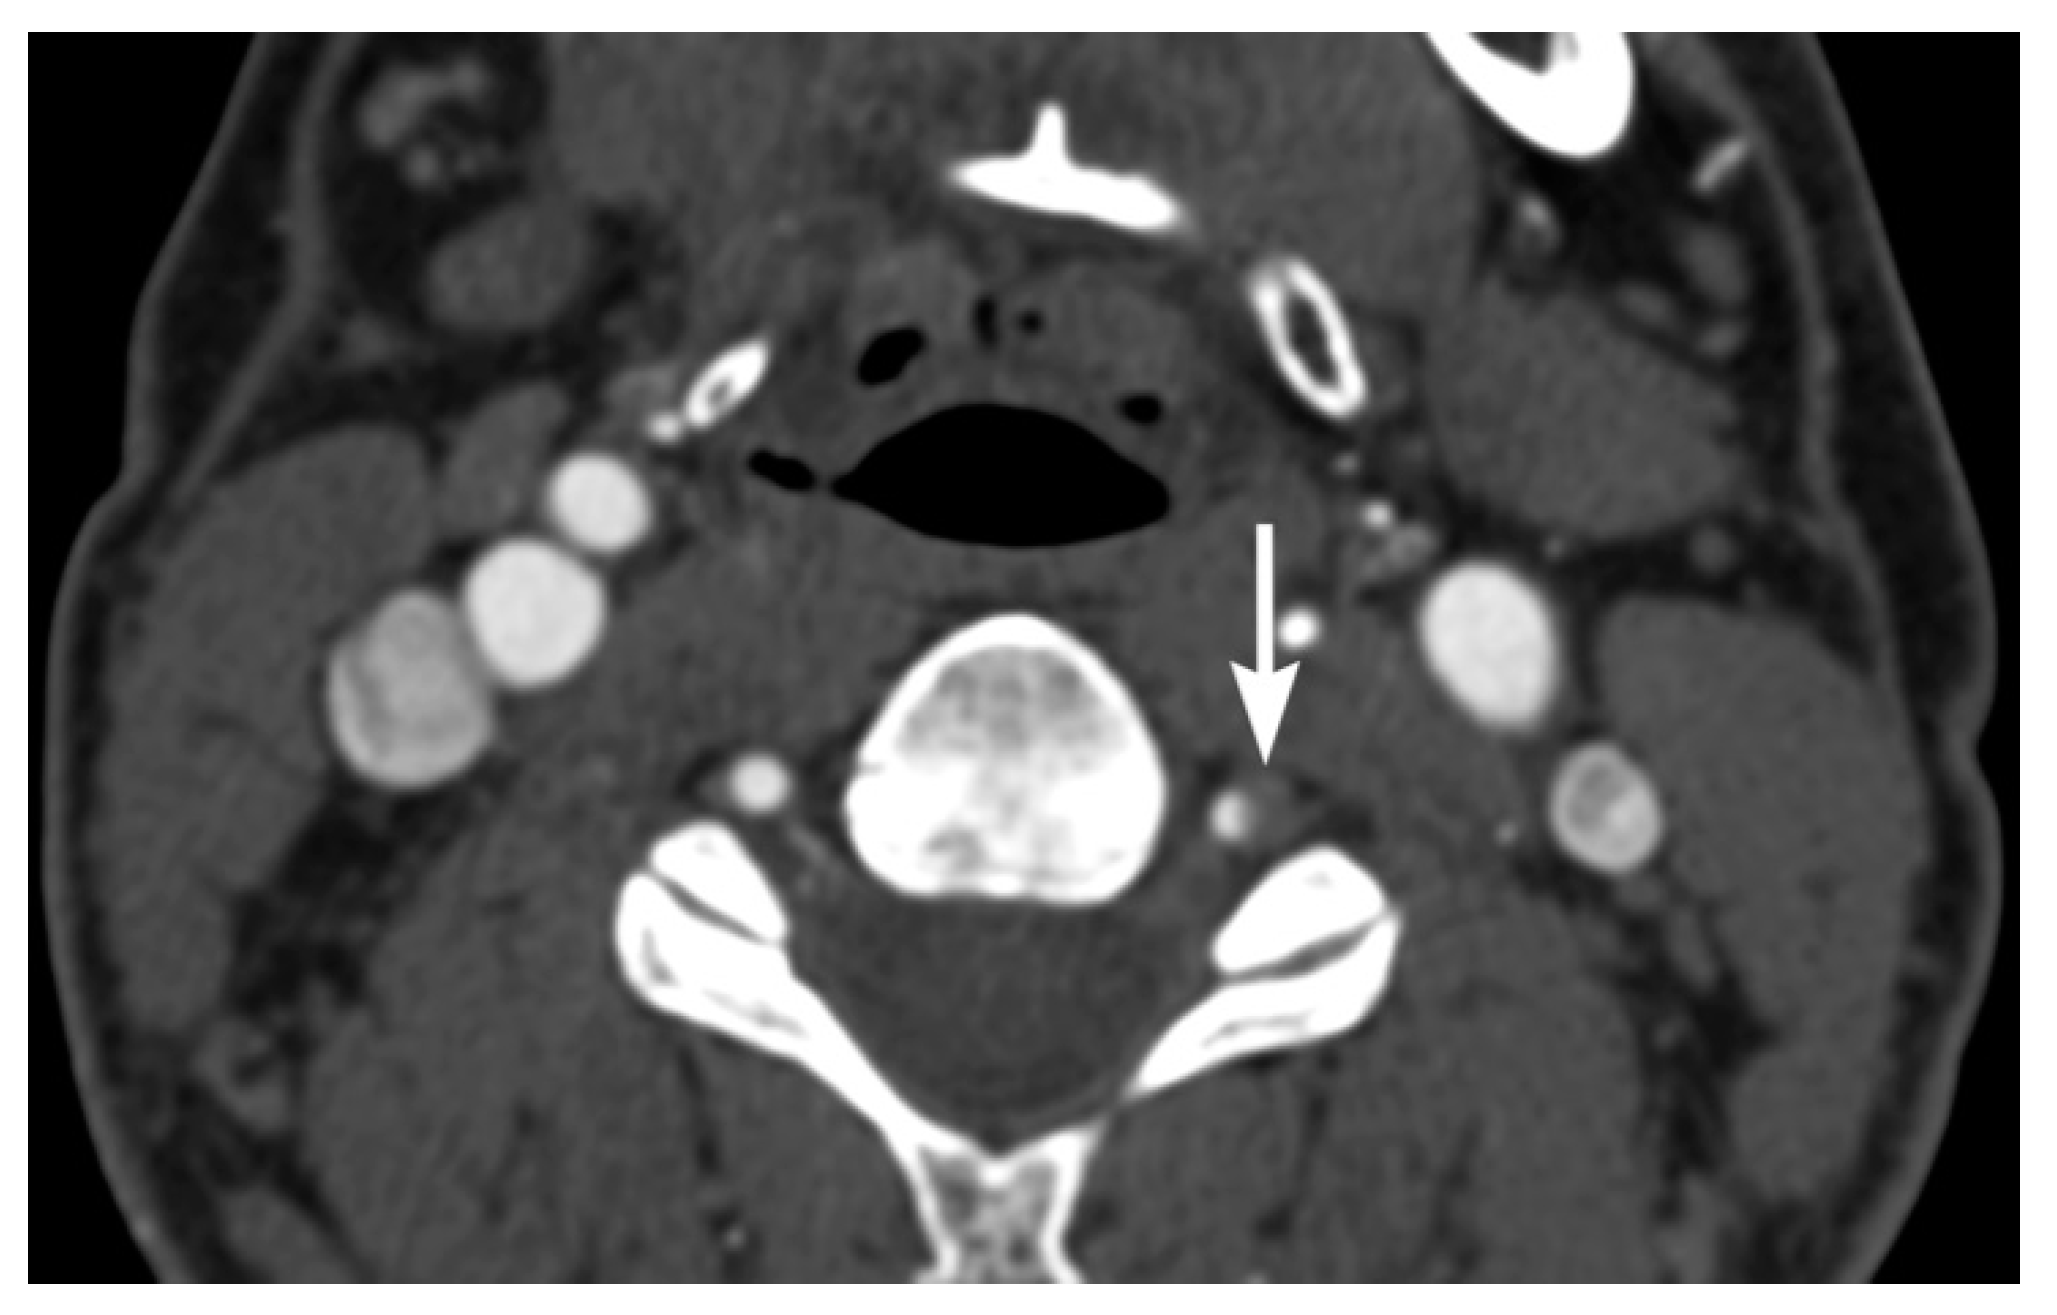

2. Imaging Techniques

3. Imaging Findings of Arterial Injury